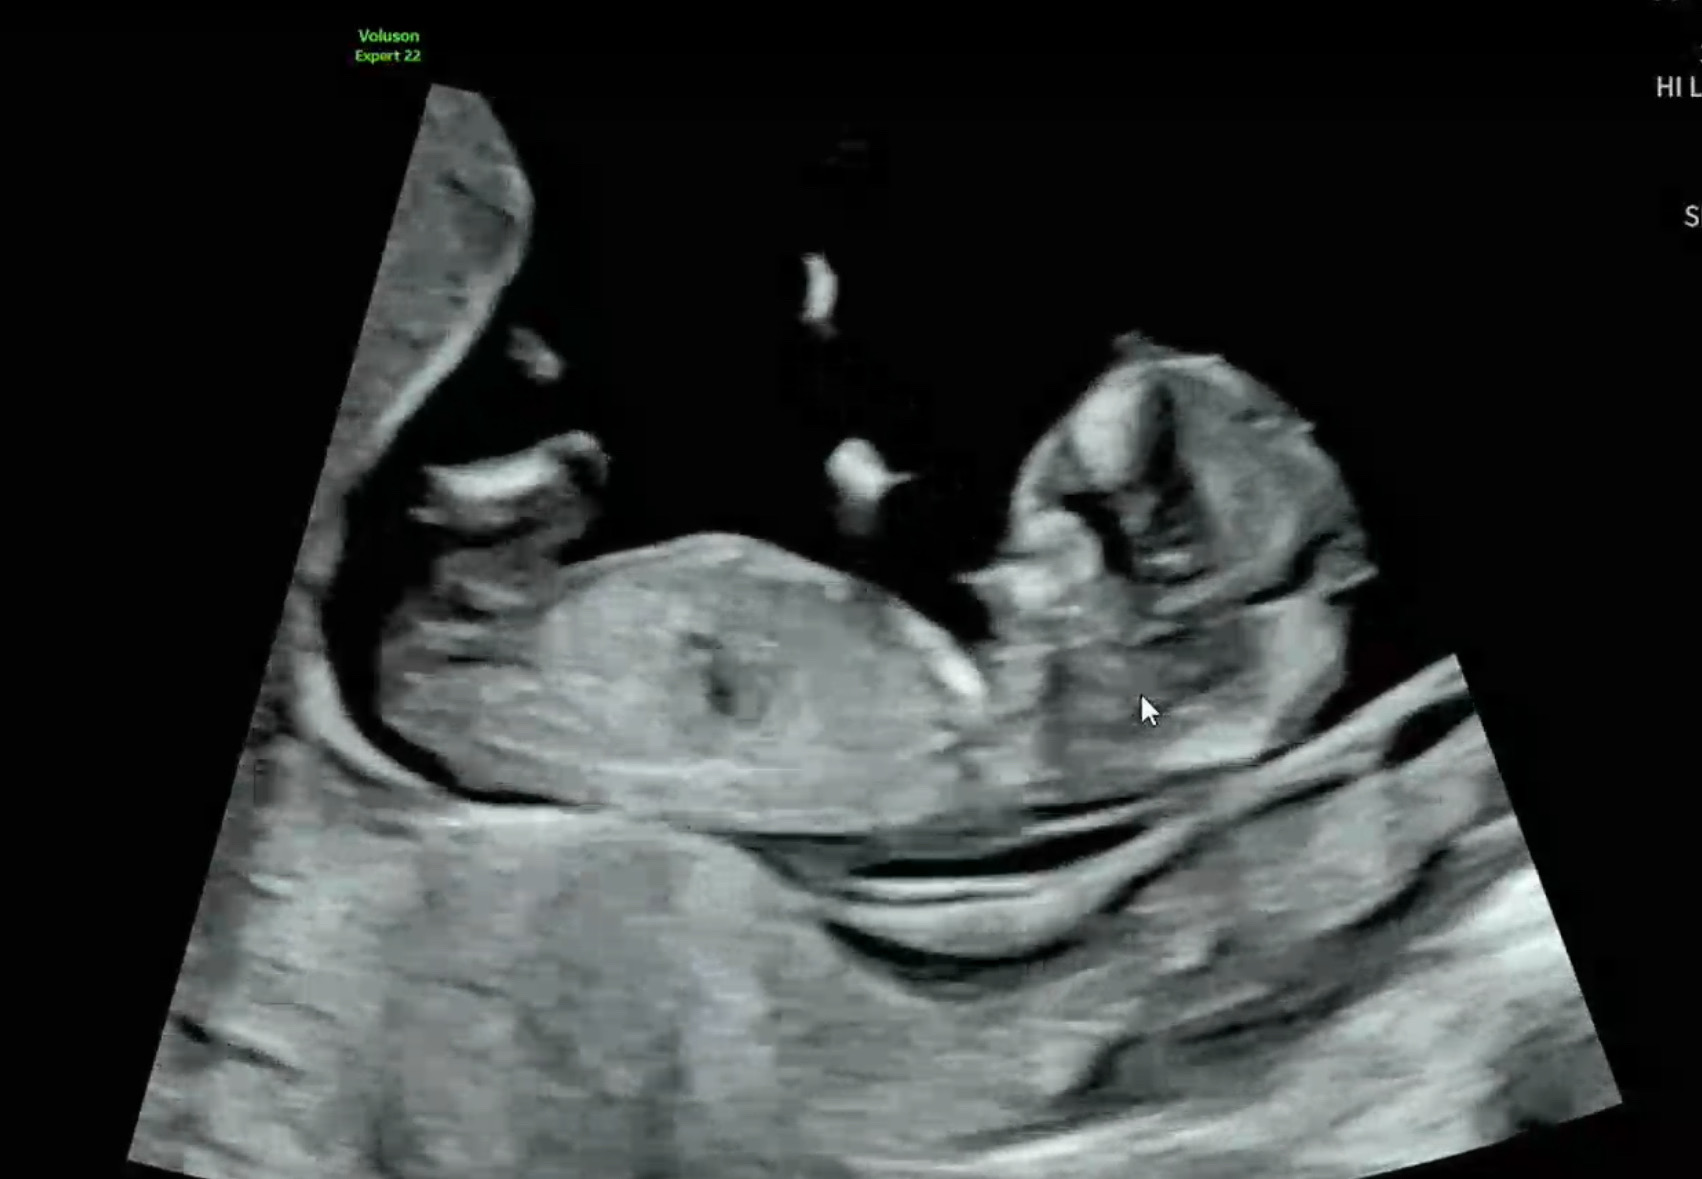

각도법 성별 예측해주세요

각도법 고수님들 투표 좀 부탁드립니다!!